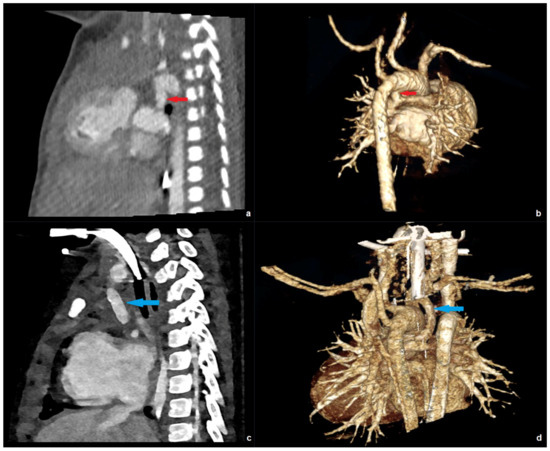

Photon-Counting CT Enables Higher Image Quality at a Lower Radiation Dose Compared with a 256-Slice Energy-Integrating Detector CT in Pediatric Patients with Congenital Heart Disease

Background/Objectives: There is an increasing need for cross-sectional imaging in pediatric patients with congenital heart disease. This patient group is highly sensitive to ionizing radiation. The purpose of this article was to evaluate differences in radiation dose and image quality between a first-generation photon-counting (PC)-CT system and a 256-slice single-source energy-integrating detector (EID)-CT in these patients. Methods: We retrospectively assessed effective dose, CT dose index-volume (CTDIvol), dose length product (DLP), and image quality of all prospectively electrocardiography-gated CTs of the thorax in all patients < 18 years of age examined between February 2021 and August 2024 (n = 43). Two independent observers subjectively scored image quality, vascular contrast, and noise on a 5-point Likert scale. In addition, we assessed the signal-to-noise-ratio (SNR) and contrast-to-noise-ratio (CNR) quantitatively. Results: All dose parameters were significantly lower in the PC-CT (n = 27) versus the EID-CT (n = 16) group (mean effective dose: 0.8 ± 0.64 versus 2.2 ± 0.88 mSv, p < 0.001; mean CTDIvol: 1.22 ± 0.96 versus 4.8 ± 1.08 mGy, p < 0.001; mean DLP: 30.7 ± 31.9 versus 73.7 ± 50.7 mGy*cm, p < 0.001). Overall subjective image quality and contrast were rated higher in the PC-CT group (p = 0.046 and < 0.001, respectively). Quantitative CNR was significantly higher in the PC-CT group (mean 39.1 ± 12.9 versus 26.2 ± 10.8, p = 0.002). Conclusions: PC-CT enables high-quality examinations for the evaluation of congenital heart disease with a highly significant dose reduction compared with a 256-slice single-source EID-CT. Full article